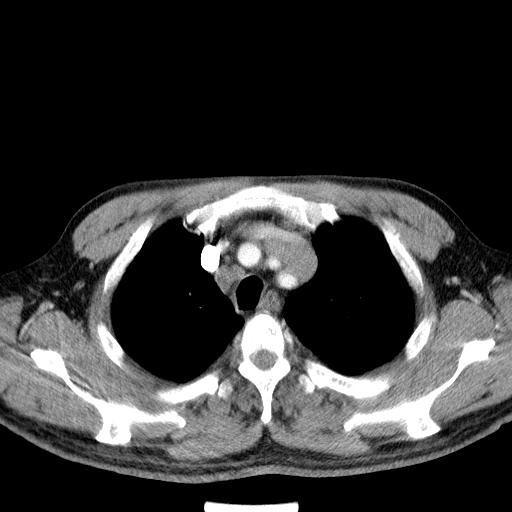

先行ct平扫,纵膈内多发软组织影,ct值约为36hu,以下为增强扫描和腹部平扫。

经典?纵膈多发肿大淋巴结。腹膜后未见异常。

还见胃窦壁增厚!转移亦有可能!

1)考虑淋巴瘤。2)双侧少量胸腔积液。